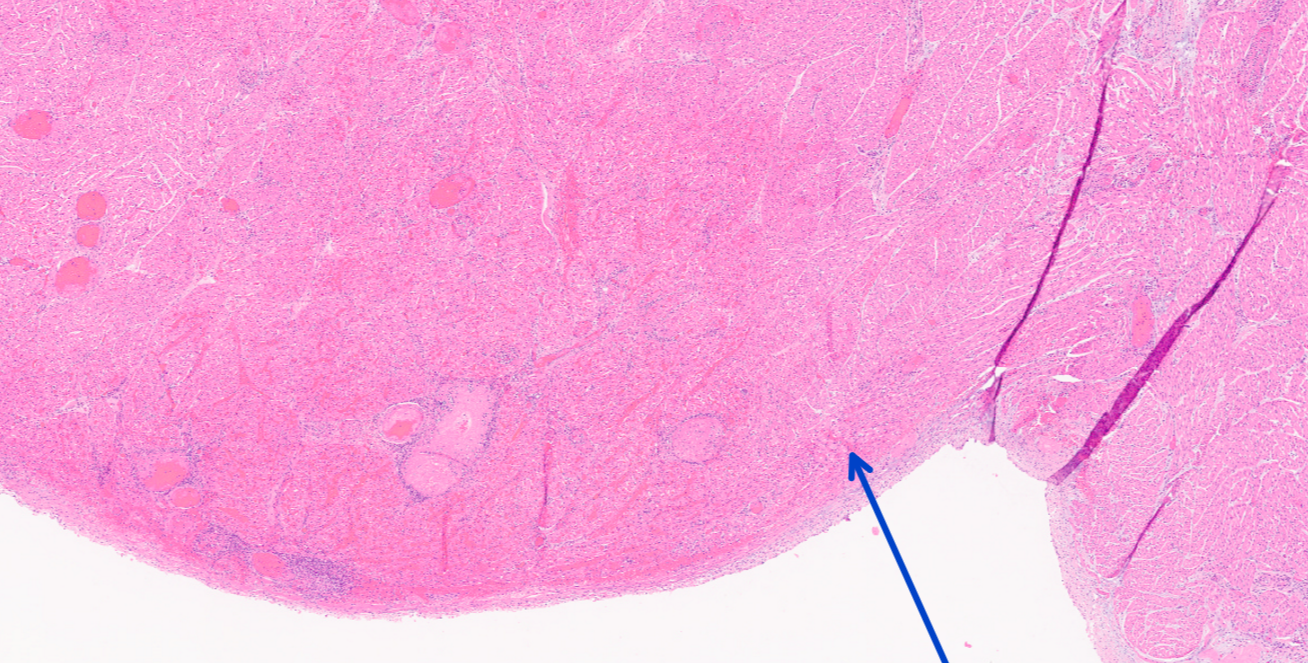

What would the morphologic diagnosis for this lesion?

acute purulent glomerulonephritis with bacterial colonies

Identify this structure:

bacterial colonies

Q

congestion

fibinous thrombosis

bacterial septic emboli